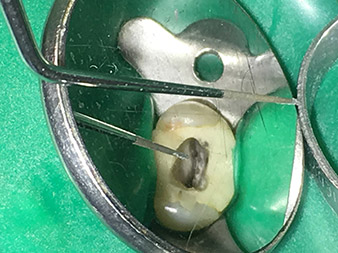

Efficient and atraumatic root canal treatment

Long-term conservation of dentition is the prime objective of modern endodontics.

Alongside efficient diagnostics and treatment methods, the use of the latest technical aids and instruments also makes an important contribution to successful patient care. Dr Shahrad Nouraie Ashtiani and his team at the practice in Bremen, Germany, treat up to ten endodontics cases a week. Patients’ desires for treatment which is as atraumatic as possible combined with good prognoses for success present a daily challenge for the dentist and oral surgery resident specializing in endodontics.

As an avid user of the expanded W&H instrument range for ultrasonic endodontics, Dr Nouraie Ashtiani is not only able to perform root canal treatments more efficiently but also to do so in a way which puts less strain on the patient. The dental expert masters even the most difficult of situations with ease. In a recent interview, the specialist in endodontics told us about the particular features which characterize the W&H instruments and mentioned possible risks which can arise in root canal treatment.

Pictures: Dr. Shahrad Nouraie Ashtiani, Bremen